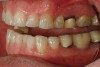

Figure 5  Preoperative retracted left lateral view of the dentition.

Figure 5